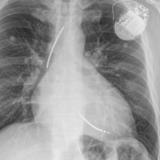

Calc Ao valve & LtA

Date: 01/26/2009

Views: 3000